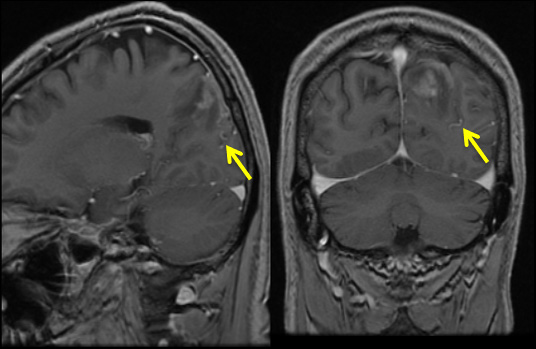

後頭葉脳表に皮質静脈に直接灌流する動静脈瘻

• 側面

• 正面

診断:Cognard Type III 硬膜動静脈瘻による静脈性梗塞(静脈高血圧性脳症)